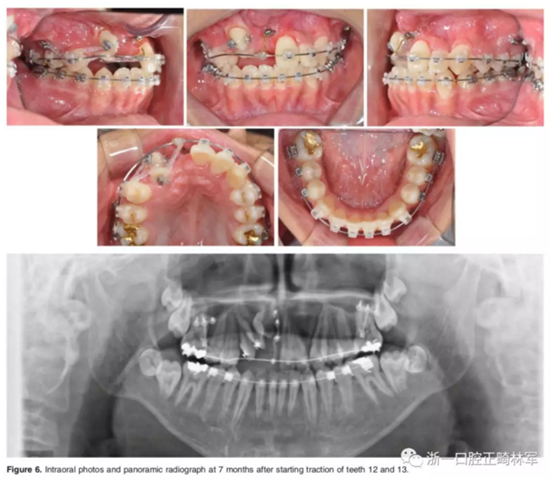

弓絲換至0.019*0.025-inch不銹鋼絲時(shí),開(kāi)始進(jìn)行外科手術(shù)暴露阻生牙。由于易位情況嚴(yán)重,三維向阻擋嚴(yán)重,因此需要行兩期手術(shù)。

一期手術(shù)主要是牽引側(cè)切牙和尖牙:于上頜前牙區(qū)唇側(cè)作切口,翻全厚瓣;腭側(cè)面較??;在尖牙唇側(cè)、側(cè)切牙腭側(cè)粘扣掛結(jié)扎絲牽引,通過(guò)一輔助鈦板及樹(shù)脂等連接至弓絲上;采用閉合式導(dǎo)萌技術(shù),將皮瓣復(fù)位縫合,僅結(jié)扎絲穿過(guò)粘膜;2周內(nèi)軟組織得以愈合,牽引開(kāi)始。先通過(guò)正畸力,近中移動(dòng)側(cè)切牙,遠(yuǎn)中移動(dòng)尖牙。10個(gè)月后,阻生牙牙冠萌出,側(cè)切牙、尖牙的易位得以矯正。

二期手術(shù)主要是牽引中切牙:于上頜前牙區(qū)腭側(cè)作切口,翻全厚瓣,在切牙唇側(cè)粘扣掛結(jié)扎絲牽引;軟組織愈合后,牽引開(kāi)始。為施加合適的垂直向力,在下頜前牙區(qū)放置C型管,掛橡皮筋牽引。14個(gè)月后,切牙牙冠萌出。使用mini管代替托槽,對(duì)切牙、尖牙進(jìn)行矯治;矯治過(guò)程采用輕力,0.014-in鎳鈦絲。